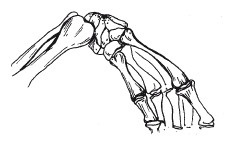

Nyolc csukló csontok formájában. A többi öt csontok - lábközép - csatlakoztassa a csukló és az ujjak. A csontokat alkotó ujjak nevezzük ujjperceket. A hüvelykujj a két, a másik 4-3. Így az egyik kéz ujjai tartalmaz 14 ujjperceket.

Csukló (szögletes közös)